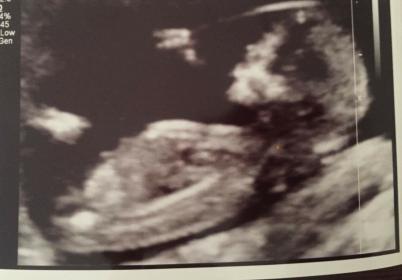

These pics are from 12 weeks 2 days . Im thinking girl but im not an expert. Would live some guesses please x Attachment 35635

Leaning boy from first pic - looks slightly angled to me

I think Boy too

Slight boy guess from me

Boy lean

Boy x

I'm leaning boy. :)

Update!! Baby is a girl!